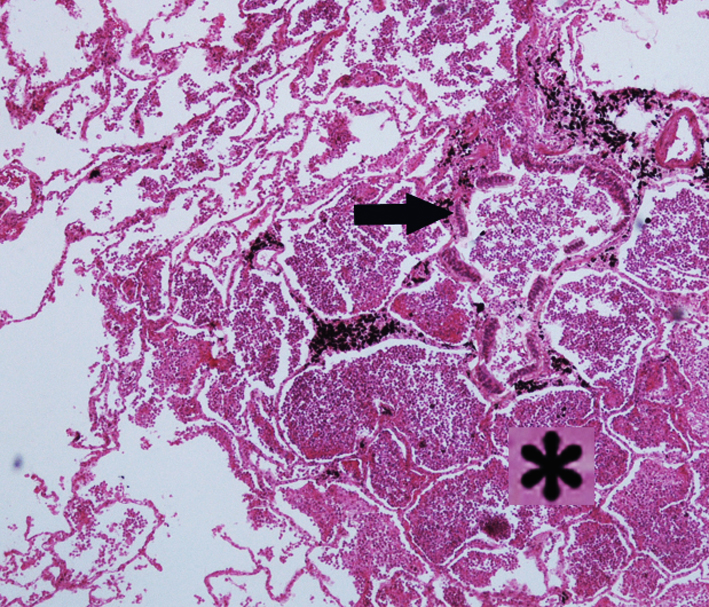

2.小叶性肺炎